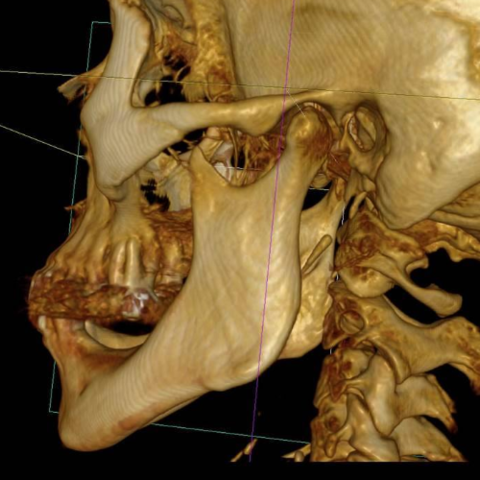

• Tomógrafo de Haz Cónico

Tomógrafo de Haz Cónico

Introducción al mercado en el año 2000 en USA pero se introdujo en 1997-1999 en Europa, con el NewTom comenzando toda una revuelta en el área medica y odontológica.